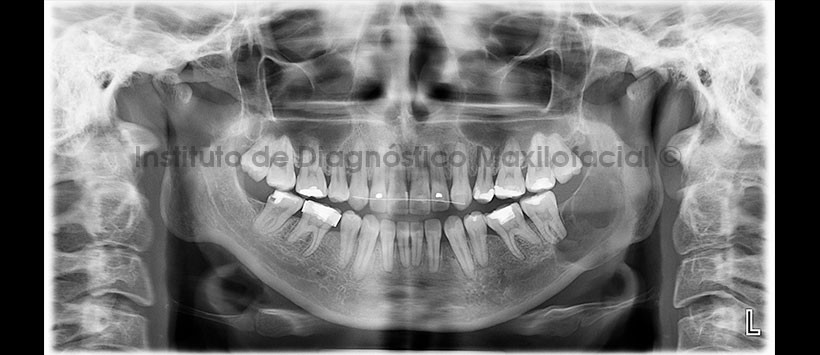

Paciente femenino de 34 años es referido al Instituto de Diagnóstico Maxilofacial para seguimiento de lesión en mandíbula. Se muestra la radiografía panorámica inicial (Figura 1), en el cual se visualizó un “hallazgo radiográfico” de una lesión mandibular de límites definidos localizado en cuerpo y rama mandibular. La paciente refiere que el examen anatomopatológico determinó el diagnostico de Granuloma Central de Células Gigantes (GCCG)